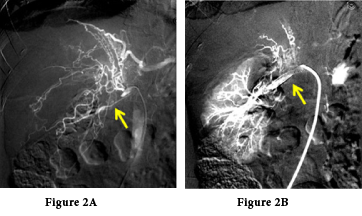

A 26-year-old female presented with severe hypertension blood pressure 190/120mmHg, with disparity in kidney size by ultrasonography (US). Doppler US revealed left renal artery dampened wave suggesting renal artery stenosis. Isotope renogram was carried out and revealed poor uptake & excretion of TC-99m-MAG3 by left kidney & impaired right kidney (Figure 1). Doppler US carotids were normal. Poor kidney function, serum creatinine 5.9gm/dl rose in two days to 8mg/dl with electrolytes imbalance; K+ 5.9mg/dl, PH 7.2 and urine output was less than 400 ml/day. Acute kidney injury was suspected, hemodialysis initiated to improve general condition and prepare patient to renal biopsy from the right kidney. However, blood pressure never been ameliorated neither pharmacological nor by ultra filtration with shooting up to 240mmHg systolic/130mmHg diastolic that endangered patient life. Tight monitoring in the intensive care unit, glyceryl trinitrate infusion was started and titrated to control blood pressure; immediate angiography was carried out once blood pressure reached 160/110mmHg and revealed long stenotic segment of left renal artery and poor-perfused kidney (Figure 2A).

Figure 2 Left renal artery angiography. A) Non perfused left kidney with severe left renal artery stenosis, collaterals are noted on angiography. B) Perfused left kidney after balloon dilatation and stent insertion on angioplasty.

Balloon angioplasty was done followed by stent insertion to maintain renal artery dilatation (Figure 2B). Patient was referred back to ICU; and blood pressure started to be under control by oral antihypertensive medications only. However, patient became anuric, hemodialysis sessions maintained to control fluid overload and improve general condition, serum creatinine reached 12.6mg/dl. Hemoglobin 8.6g/l but with no evidence of bleeding, erythropoietin was not initiated because of hypertension. In the following days blood pressure improved dramatically that enabled successful weaning of antihypertensive medications, urine output started to increase with spontaneous drop of serum creatinine without performing hemodialysis. In two weeks, blood pressure was maintained at systolic 120mmHg/80mmHg diastolic without antihypertensive medication with normal serum creatinine 1.1mg/dl and hemoglobin 11g/l on discharge from hospital (Figure 3).